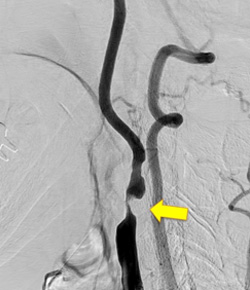

写真左:頚動脈狭窄所見

写真右:ステントを用いて狭窄部を拡張し治療